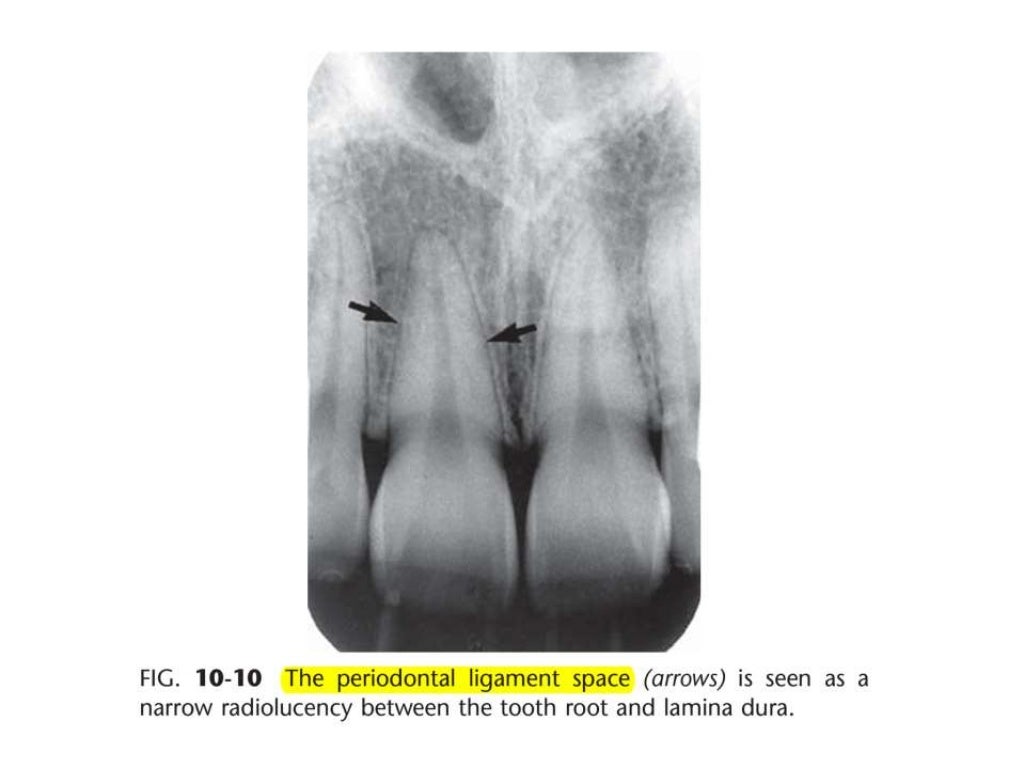

Intraoral radiographic anatomy Intraoral Radiographic Anatomy Quizlet this chapter will deal with the basic terms of intraoral radiographic anatomy and key features in identifying. study with quizlet and memorize flashcards containing terms like nasal septum, nasal fossa, nasal spine and more. intraoral radiographic anatomy — quiz information. learn about radiographic film from intraoral radiographic anatomy dental ce course & enrich your knowledge in. Intraoral Radiographic Anatomy Quizlet.

Intraoral Radiographic Anatomy Intraoral Radiographic Anatomy Quizlet For each question select the correct response;. this chapter will deal with the basic terms of intraoral radiographic anatomy and key features in identifying. Lingual foramen, nutrient canals, mental ridge, and inferior border of the. study with quizlet and memorize flashcards containing terms like radiolucent is: Identify the different sizes of radiographic receptors. study with quizlet and. Intraoral Radiographic Anatomy Quizlet.